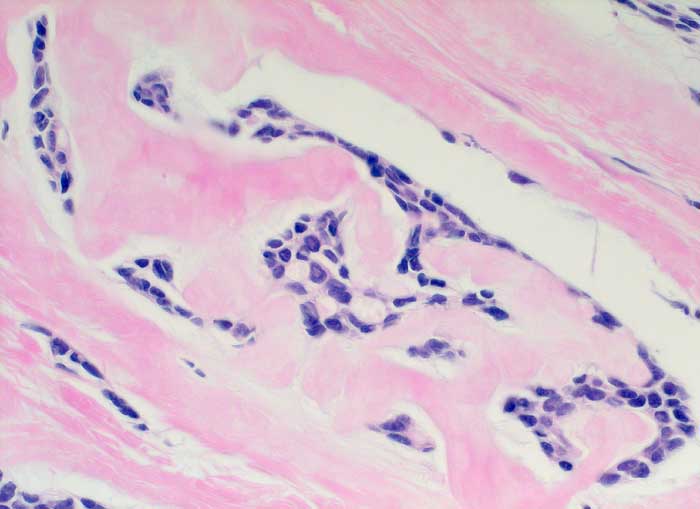

Einleitung

Adenoidzystische Karzinome machen lediglich 1% aller Mammakarzinome aus. Die Morphologie ist identisch mit dem gleichnamigen Tumor der Speicheldrüsen. Die Zellen des adenoidzystischen Karzinoms bilden kohäsive Verbände und Drüsen oder mikrozystische Strukturen. Die Tumorzellen sind klein und monomorph, die Kern-Zytoplasmarelation ist hoch. Die Kerne sind dunkel, rund bis oval oder angulär und enthalten bisweilen einen kleinen Nukleolus. Azelluläre hyaline Körperchen aus mucoidem Material, welche die Hohlräume der intakt aspirierten kribriformen Strukturen ausfüllen, sind besonders typisch. Das mucoide Material kann auch verzweigte oder fingerartige abgerundete Strukturen ausbilden.